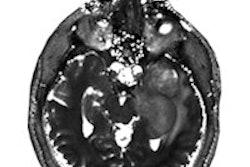

Case Western has been developing a technology called magnetic resonance fingerprinting to improve the accuracy of MRI. It features a constantly varying sequence of pulses to create quantitative maps for characterizing tissues. The challenge is how to identify the best sequence of MR pulses and readouts to achieve the best scan efficiency.

Microsoft will optimize pulse sequences by mapping them to a form that is compatible with quantum computers; it will then use that algorithm to enhance the diagnostic capability of MRI. Microsoft HoloLens will also be used to create a 3D holographic model of the results.